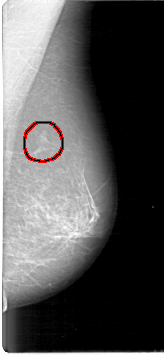

FILE: D_4097_1.LEFT_MLO.OVERLAY

TOTAL_ABNORMALITIES 1

ABNORMALITY 1

LESION_TYPE MASS SHAPE IRREGULAR MARGINS ILL_DEFINED

ASSESSMENT 2

SUBTLETY 3

PATHOLOGY BENIGN

TOTAL_OUTLINES 1

BOUNDARY